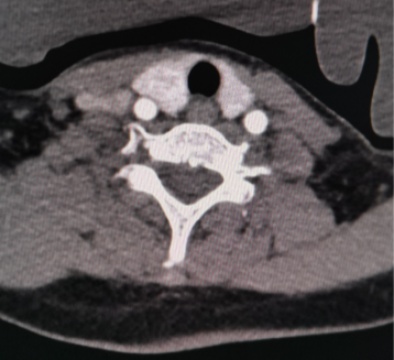

(a) (b) (c) (d)

(a)~(d)甲状腺滤泡性腺瘤患者双能量CT增强扫描动脉期原始图像、碘图、Rho/Z图及病理图

Figure 1. Examples of dual-energy CT arterial phase images, iodine uptake images, Rho/Z images, and pathological findings in three groups of patients with thyroid nodules (HE, ×100, H) (Rho/Z, Electron Density/Effective Atomic Number)

1. 三组甲状腺结节患者双能量CT动脉期图、碘图、Rho/Z图及病理图示例(HE, ×100, H) (Rho/Z,电子密度云/有效原子序数)